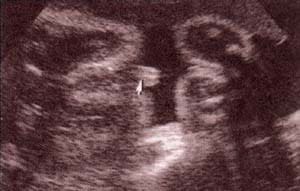

Diagnóstico Prenatal -  genitales externos xx Diagnóstico Prenatal -  genitales externos xx

fig. 49. – (c). 30 semanas. labios. fig. 49. – (d). 38 semanas. labios mayores (1) nótese la hipertrofia del clítoris (2).